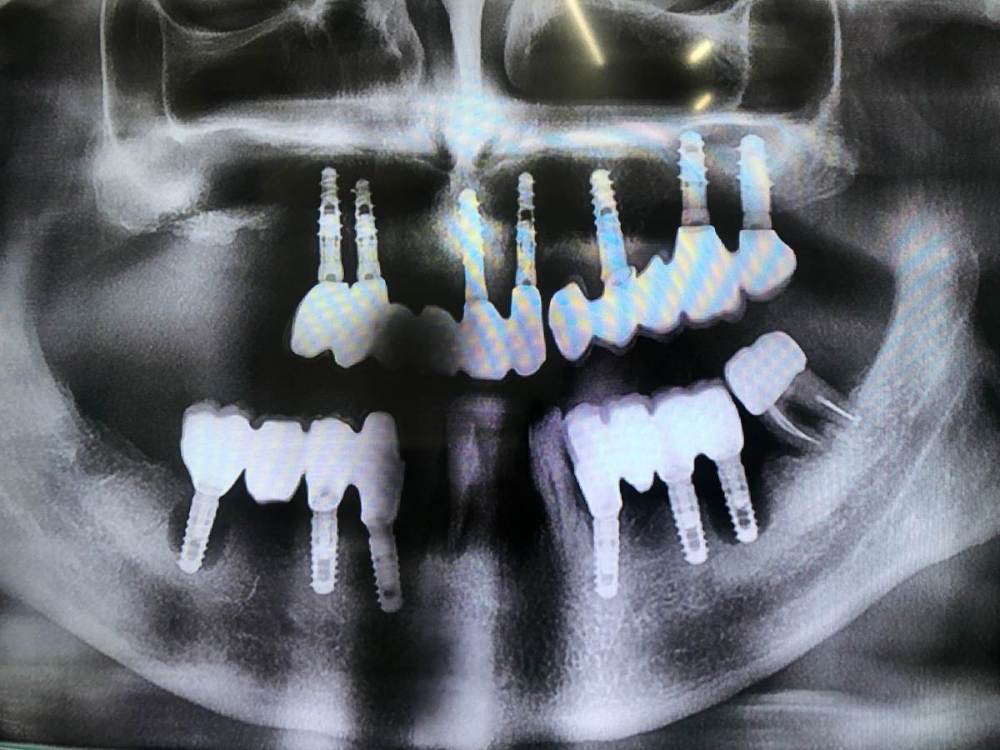

Уважаемые коллеги! Помогите, пожалуйста, опознать винты с нижней челюсти) пациент из Италии, крутил их лет 10 назад, никакой документации нет

За качество прошу прощения, завтра смогу залить получше, но сегодня пока так, а дело срочное)